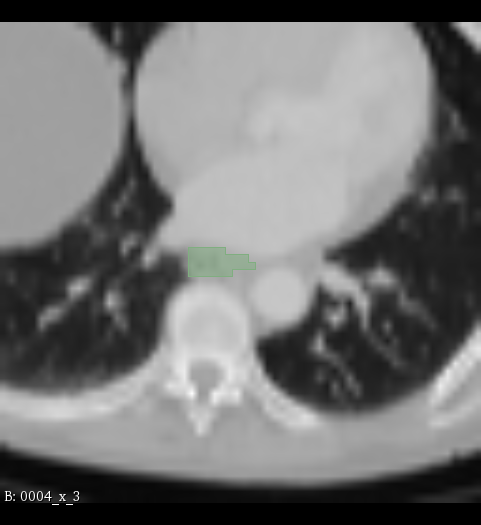

Figure 2: Illustration of the data from the TotalSegmentor data set [32] used in the experiments. The first row shows the axial, coronal and sagittal views passing the center of mass of the kidney in one of the data points. The second row shows the axial, coronal and sagittal views passing the center of mass of the aorta in one of the data points. The third row shows the axial, coronal and sagittal views passing the center of mass of the esophagus in one of the data points.

5.1 Data

The experiments are conducted with respect to the TotalSegmentor data set [32]. This data set contains 1204 CT images with 104 anatomical structures (27 organs, 59 bones, 10 muscles, 8 vessels). To illustrate the effect noise may have on organs with different shape, three different organs are chosen. This includes the right kidney which in general is pretty spherical, the aorta which is tubular and relatively thick and the esophagus which is tubular and relatively thin. For each of the organs, 400 cases is selected and split into 5 folds of 80 cases. Finally, the images are sub-sample to half resolution and patches of 643superscript64364^{3} voxels centered in each of the structures are extracted.